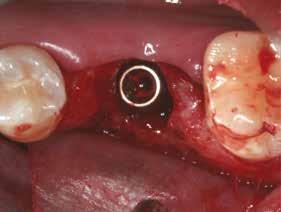

A részleges extrakció befejezése után következhet az implantátumágy preparálása a gyártó utasításai szerint (6.

kép). A bemutatott esetben Nobel Replace CC 4,3x13mm implantátumot helyeztünk be, amely a bukkális oldalon direkt kontaktusba került a megmaradt foggyökérdarabbal (7. kép). Az alveolus oldalfalai és a körszimmetrikius implantátum közötti hézag kitöltésére bovin eredetű xenograftot (Creos S xenogain) használtunk (8. kép). A hasonló

A behelyeztt implantátum primer stabilitását megfelelőnek ítéltük (kb. 40 Ncm) az azonnali terheléshez (9. kép).

Az extrakciót megelőző szituációs lenyomat alapján gyári, titán, ideiglenes abutment felhasználásával, a szék mellett készített, csavaros rögzítésű, azonnali akrilát ideiglenes koronával láttuk el, melyet 20 Ncm nyomatékkal rögzítettünk (10. kép). Az azonnali terhelés szabályainak megfelelően, az ideiglenes korona nem volt kontaktusban a szomszédos és az antagonista fogakkal.